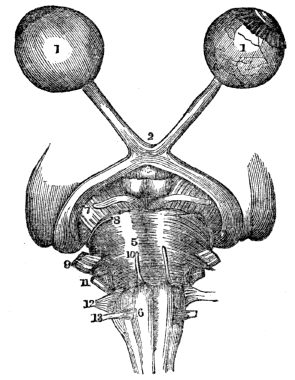

| 44. | Anatomy of the Organs of Vision, | 394 |

| 45. | Physiology of the Organs of Vision, | 404 |